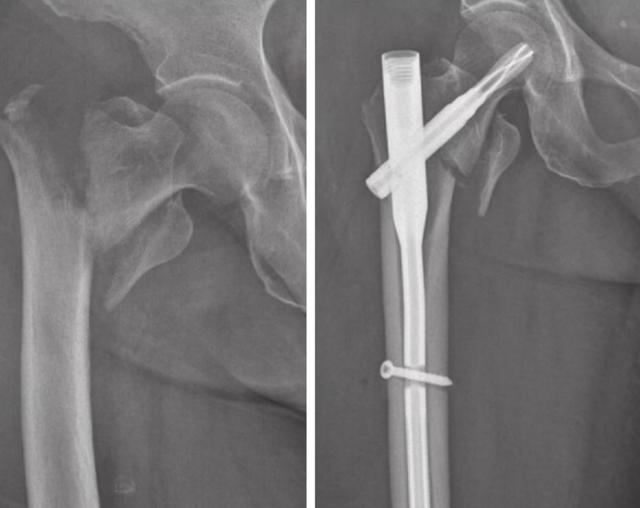

陈奶奶今年86岁,由于腿脚不便不慎摔倒,伤及右髋部,伤后感疼痛,活动受限,无法站立,检查显示:右侧股骨粗隆间骨折;高血压病(3级/高危);2型糖尿病;双膝骨性关节炎;右大腿压疮。

术前,对陈奶奶进行全面评估、完善检查,排除手术禁忌,以保证手术前陈奶奶的身体状况符合手术要求,手术耗时约35分钟,给予骨折完美复位,坚强固定。

术前、术后

术后给予陈奶奶复查拍片良好,通过麻醉科、重症科等共同努力,给予进行指导康复,陈奶奶进行积极功能康复,待骨折愈合以后会有一个良好的功能。

罗伟田副主任医师建议:股骨粗隆间骨折在临床中非常常见,通常发生于老年患者,老年患者通常合并高血压、糖尿病、脑梗等多种内科疾病,保守治疗经常引起长期卧床并发症,如坠积性肺炎,压疮,泌尿系感染,下肢深静脉血栓等,大多数患者在半年内失去生命,所以如果患者身体条件允许,建议尽量行手术,现在普遍采用闭合复位髓内针微创治疗,手术后患者能尽快恢复活动,避免长期卧床的一系列并发症,通常需要高超的显微技术和丰富的临床经验,通过各个科室配合,尽快的进行和完成手术,越早进行手术效果越好,术后控制感染,通过后期积极康复,取得一个较好的临床效果,希望大家以后注意安全,一旦发生类似情况,请及时就医。